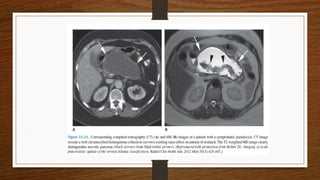

• CECT is indicated in following :

1. If there is diagnostic uncertainty.

2. In patients with severe acute pancreatitis, to distinguish interstitial from

necrotising pancreatitis

3. Severity of pancreatitis detected on CT be staged a/c to balthazar score

4. In patients with organ failure,signs of sepsis and clinical deterioration

5. When localized collection is suspected,fluid collection,psuedocyst

• MRI and MRCP ,are used increasingly to diagnose and assess severity

• MRI appears to be comparable to CT :

As effective as CT in demonstrating presence and extent of pancreatic necrosis

and fluid collection

Regarding the severity of the disease

Probably superior for indicating the suitability of collections for non surgical

drainage